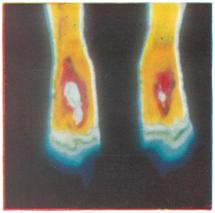

Рис. 15.

Цветная термограмма стоп при отморожении пальцев III—IV степени; поля изотермы синего цвета соответствуют областям поражения в которых инфракрасное излучение подавлено.

Уже в первые недели после отморожения (то есть раньше, чем каким-либо другим методом) с помощью инфракрасной термографии удается выявить зоны, подвергающиеся деструктивным процессам. На термограммах они определяются в виде участков ослабленной или подавленной радиации на фоне интенсивного излучения областей, захваченных реактивным воспалением (рис. 18). С помощью цветной термографии при отморожении возможна точная характеристика нарушения циркуляции в пораженных тканях. При этом поля различных изотерм определяются цветом, и граница нежизнеспособных и плохо снабжаемых кровью тканей выявляется весьма четко (рис. 11).